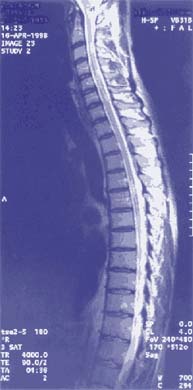

Ressonância nuclear magnética

Ressonância Magnética Nuclear